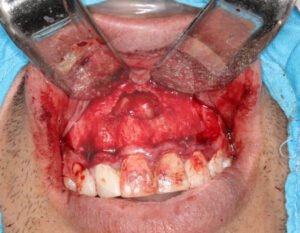

Un absceso es una acumulación de infección que puede causar dolor intenso e inflamación. Cuando el proceso infeccioso no mejora con tratamiento convencional, puede ser necesario realizar un drenaje o manejo quirúrgico.

El tratamiento depende del origen y gravedad de la infección. Puede incluir medicamentos, drenaje quirúrgico o procedimientos específicos para eliminar el foco infeccioso y evitar complicaciones.

En casos de mayor complicación deberá ser ingresado a cuidados hospitalarios, y programar el procedimiento quirúrgico que corresponda